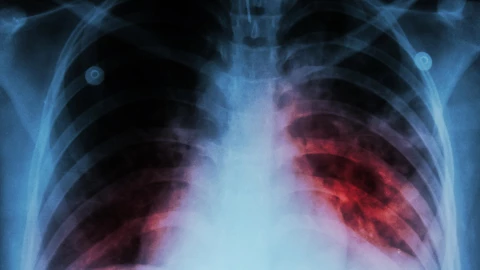

Especialistas en salud pública advierten que una persona con tuberculosis sin diagnóstico ni tratamiento puede contagiar hasta a 15 personas en un año. La enfermedad afecta principalmente los pulmones, aunque también puede presentarse en riñones, cerebro, sistema digestivo, columna o piel.